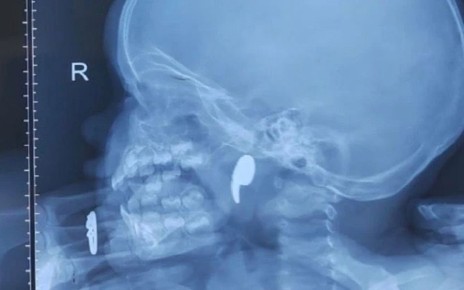

Операцию провели специалисты областной больницы №1 вместе с врачами Бобровской РБ. Внедрение эндокардиального стимулятора было необходимо для коррекции патологии у 86-летней пациентки, страдающей полной поперечной блокадой сердца и приступами потери...